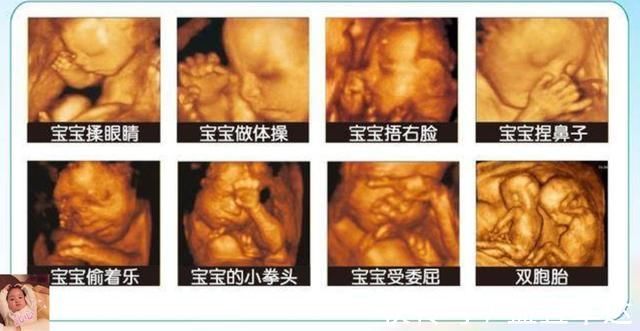

当然宝宝还会做其他一些事情,比如做个鬼脸、吮吸手指等等,胎宝宝表示:小日子开心到飞起!